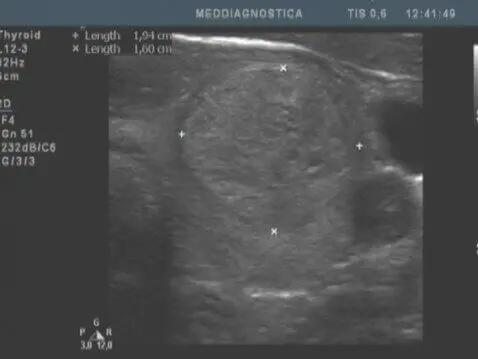

УЗД щитовидної залози. Один і той же пацієнт, дослідження щитовидної залози з інтервалом в 3 роки, збільшення вузла з розмірів 11х7х10 мм до 26х17х19 мм. Освіта визнано доброякісним. (Різниця в кольорі знімків – розрив апарати)